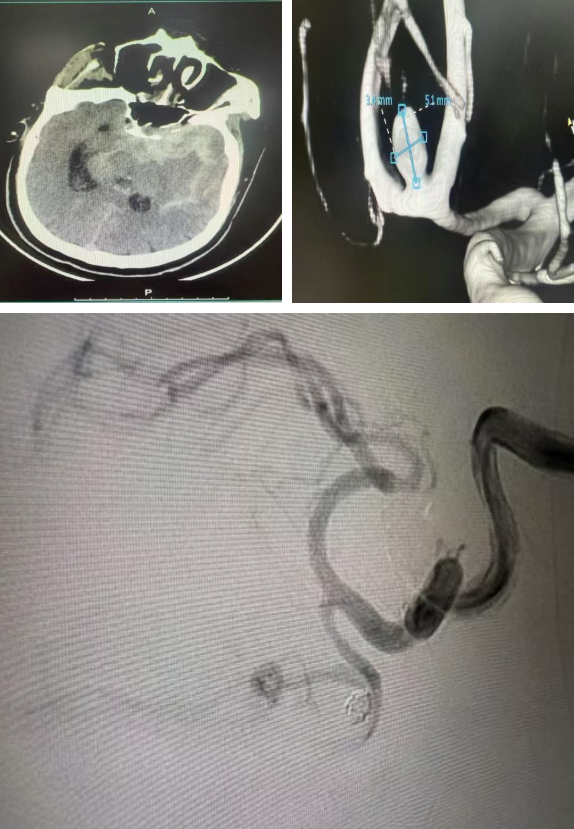

病情进展超出预期——就诊途中患者意识迅速恶化至昏迷。医院立即启动急诊绿色通道,急诊科医护团队第一时间为其实施气管插管、呼吸机辅助呼吸,同时紧急安排头颈部及主动脉CT血管造影(CTA)检查。检查结果让所有医护人员神经紧绷:患者同时罹患颅内前交通动脉瘤破裂与Stanford B型主动脉夹层,两种疾病单独发生时致死率已极高,叠加出现在临床上极为罕见。

完善术前准备后,神经外科曾实主任医师、张伟医师率先登台,全脑血管造影术精准定位动脉瘤形态与位置。在麻醉团队全程维持血流动力学平稳的护航下,手术医师将数枚超软弹簧圈精准送入动脉瘤腔内,直至实现完全致密栓塞。术后造影显示,动脉瘤彻底“消失”,载瘤动脉及分支血流通畅,第一阶段攻坚告捷。

▲神经外科手术造影显示载瘤动脉及分支血流通畅

短暂的术后稳定期内,麻醉监护团队将患者血压精准控制在安全区间,为下一阶段手术筑牢基础。随后,甲状腺乳腺血管外科文飞主任医师、段成主治医师接力开展“胸主动脉覆膜支架腔内隔绝术”。术中,医护团队精准操控输送系统,将覆膜支架成功释放于降主动脉夹层破口处,完美覆盖原发撕裂口。术后造影证实,破口封堵满意,假腔血流显著减少,真腔及重要分支血管血供完好,第二阶段手术同样圆满成功。

▲甲状腺乳腺血管外科手术造影显示破口封堵满意